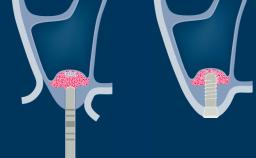

- describe how implant positioning can lead to esthetic complications

- describe other factors that may contribute to esthetic complications